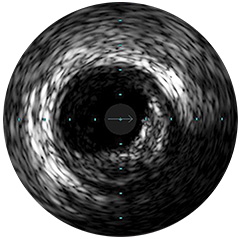

Figura 1